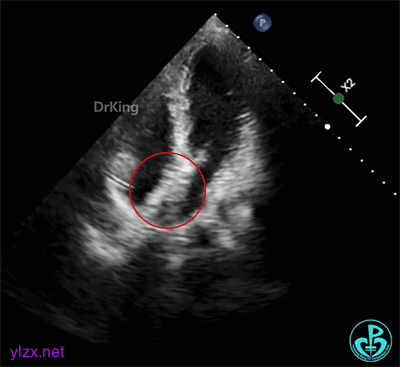

右心声学造影检查:微泡造影剂经右肘正中静脉、上腔静脉进入右房,充盈良好,可见小楔形负性充盈区,患者瓦氏呼吸后见细小微气泡自裂隙处进入左房,约25~30个,一个裂隙位于卵圆孔入口处,一个位于卵圆孔出口处。

经食道超声三维、二维和右心声学造影图像: